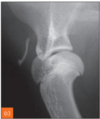

What do you see

Condylar fractures Lateral: most common Medial: rare Y or T: fracture line goes through and between condyles..